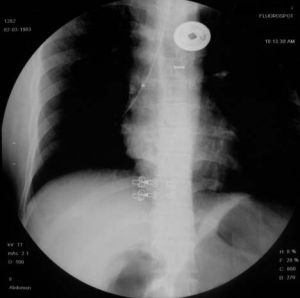

(4)胸部X線檢查用透視、後前位胸片、前弓位攝片、點片、肺尖部攝片、斷層攝片。

(5)CT選擇性運用CT對肺結核診斷可彌補胸部X線檢查的不足。